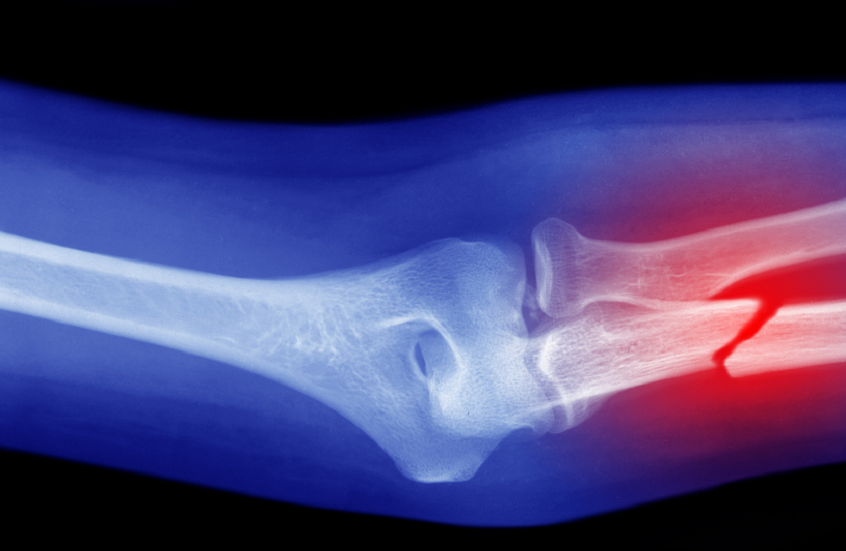

صورة تعبيرية / Peter Dazeley / Gettyimages.ru